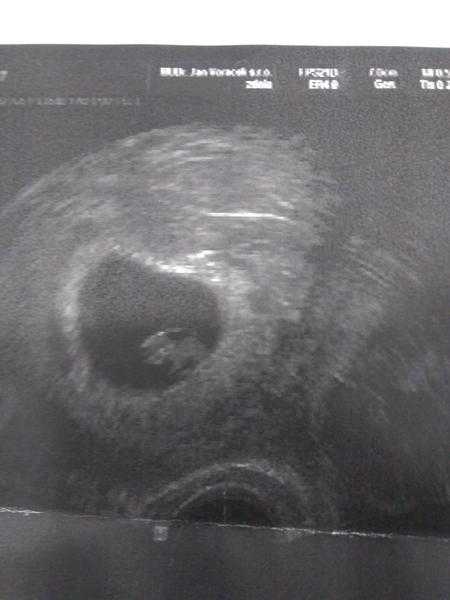

Tady fakt není prakticky nic vidět, vyfotím to pak kdyžtak za denního světla.